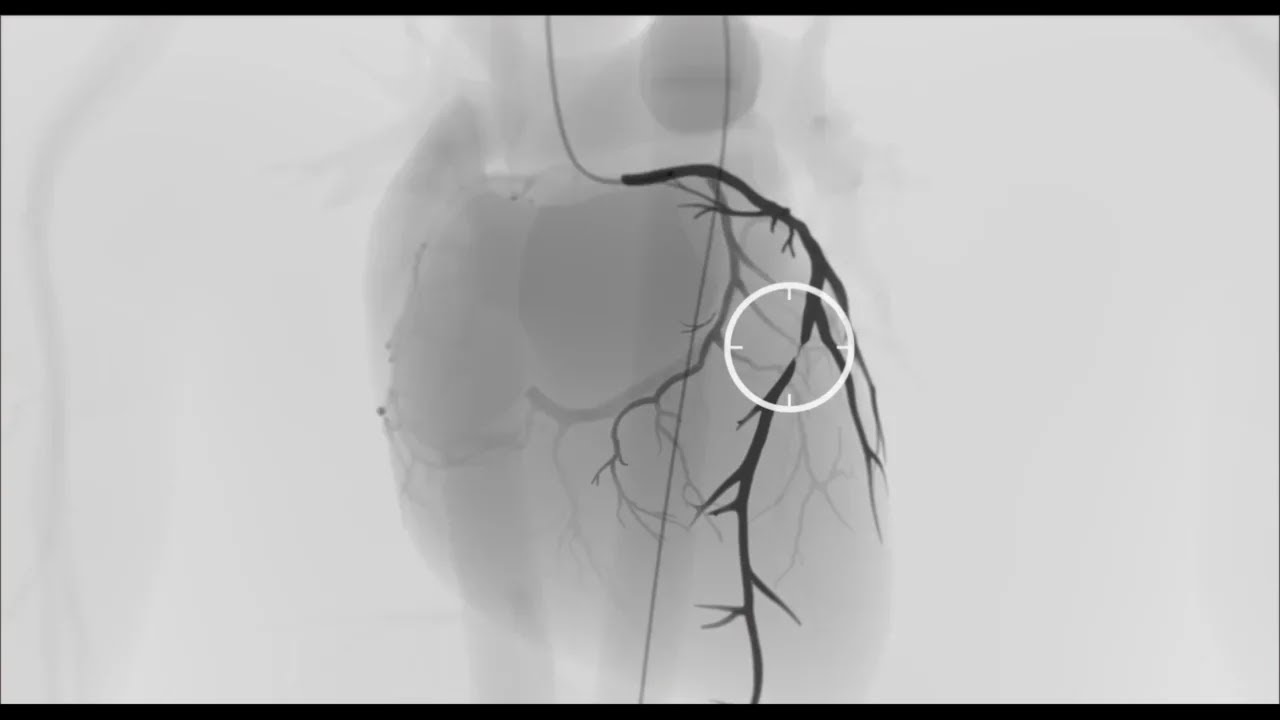

-Kalp damarlarının görüntülenmesi (Anjiyo; koroner anjiyografi)

-Kalp damarlarındaki darlık ve tıkanıklarının stent ile ameliyatsız açılması [Kronik tam tıkanıklıklar (CTO), LMCA, Rotapro, IVL ve çatallı damarlar (bifurkasyonlar) dahil tüm kompleks stentleme işlemleri]

Koroner Anjiyogram

Koroner Anjiyoplasti